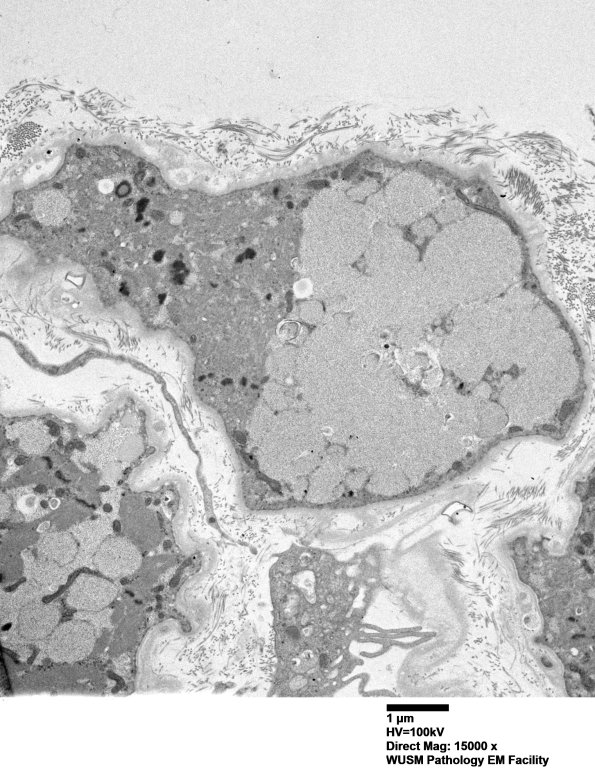

5D9,10 This atrophic fiber shows little residual of its sarcomeric substructure. (electron micrographs)